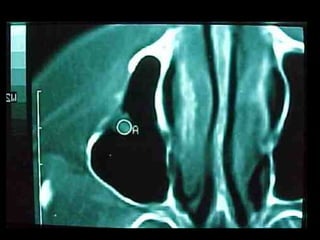

Eliminación de focos sépticos en bloque en paciente con osteitis

mandibular crónica

Osteitis

Imagen microscópica de osteitis, inicialmente existe una etapa de

osteoclastosis seguida por regeneración. No siempre el hueso

regenera en su totalidad y sigue el curso de cualquier inflamación

dejando un area de tejido fibroso que con el tiempo puede

calcificarse (hueso denso)

Manejo con antibióticos obligado

Revisión periódica

Osteomielitis

La osteomielitis es una infección súbita o de larga data del hueso o médula

ósea, normalmente causada por una bacteria piógena o micobacteria y

hongos. Los factores de riesgo son trauma reciente, diabetes, hemodiálisis y

drogadicción intravenosa.

La Osteomielitis se define como una inflamación extensa del hueso,

implicando a toda porción esponjosa, medular, cortical, periostio, vasos

sanguíneos, nervios y epífisis. La inflamación puede ser aguda, subaguda o

crónica y presenta un desarrollo clínico diferente según su naturaleza (1-5).

En el caso de los maxilares se considera la infección odontógena como la

causa más frecuente de osteomielitis. Se puede presentar a cualquier edad

con un predominio entre los hombres. Afecta principalmente al maxilar

inferior. En el maxilar superior es más raro, debido a una mayor

vascularización .